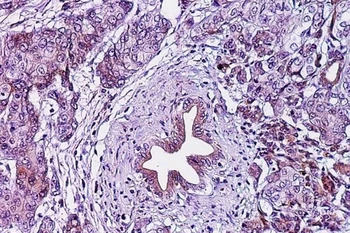

Lớp cắt biểu bì ung thư tuyến tụy. (Nguồn: eurekalert.org)

Tìm ra phương pháp giúp ngăn ngừa sự tiến triển của ung thư tuyến tụy